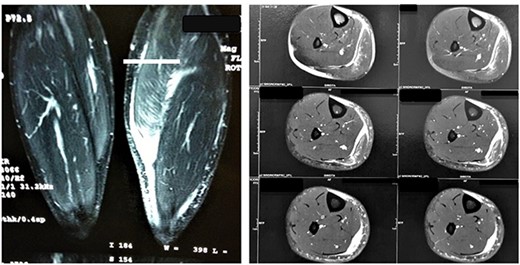

MRI images of Patient 1 and Patient 2, respectively. In the left image, a coronal section of the two legs weighted in a sensitive liquid sequence shows edema accompanied by a distal gap in the lesion topography. In the right image, we see multiple axial slices also showing fluid accumulation and muscle retraction in the musculotendinous transition.